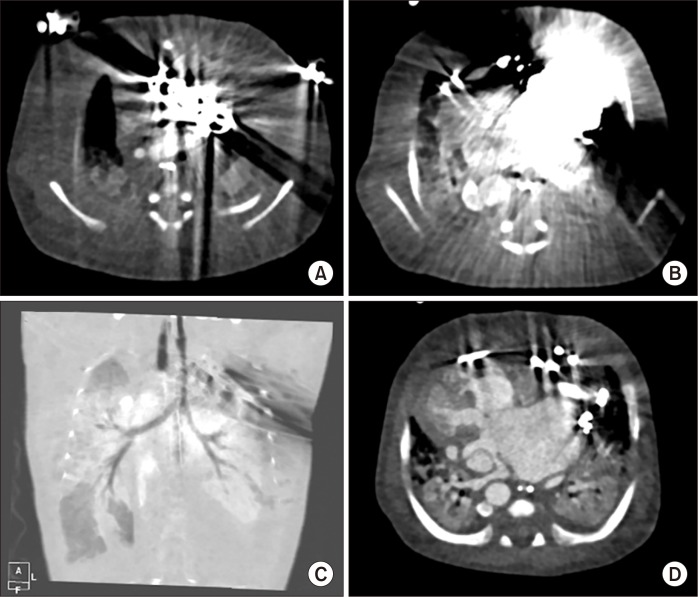

A Case Report of Rare Complications after Epicardial Permanent Pacemaker Implantation in an Infant: Airway Compression, Skin Necrosis, and Bowel Perforation.

Insertion of an epicardial pacemaker is a useful treatment for pediatric patients with an abnormal heart rhythm. However, there are limitations and concerns when implanting epicardial pacemakers in infants and neonates due to their small body size. We report a patient who experienced rare complications after implantation of a permanent pacemaker.